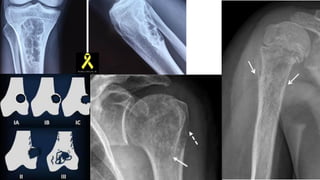

• Well-defined oval lucent lesion

• • S i z e = 1-10 c m

• Position- eccentric in the epiphyses

• Margin- thin sclerotic rim

• • Cortical expansion = +-

• Periosteal r e a c t i o n = +-

• Internal calcification = about quarter of cases = stippled calcification

Plain radiograph and CT Scan features